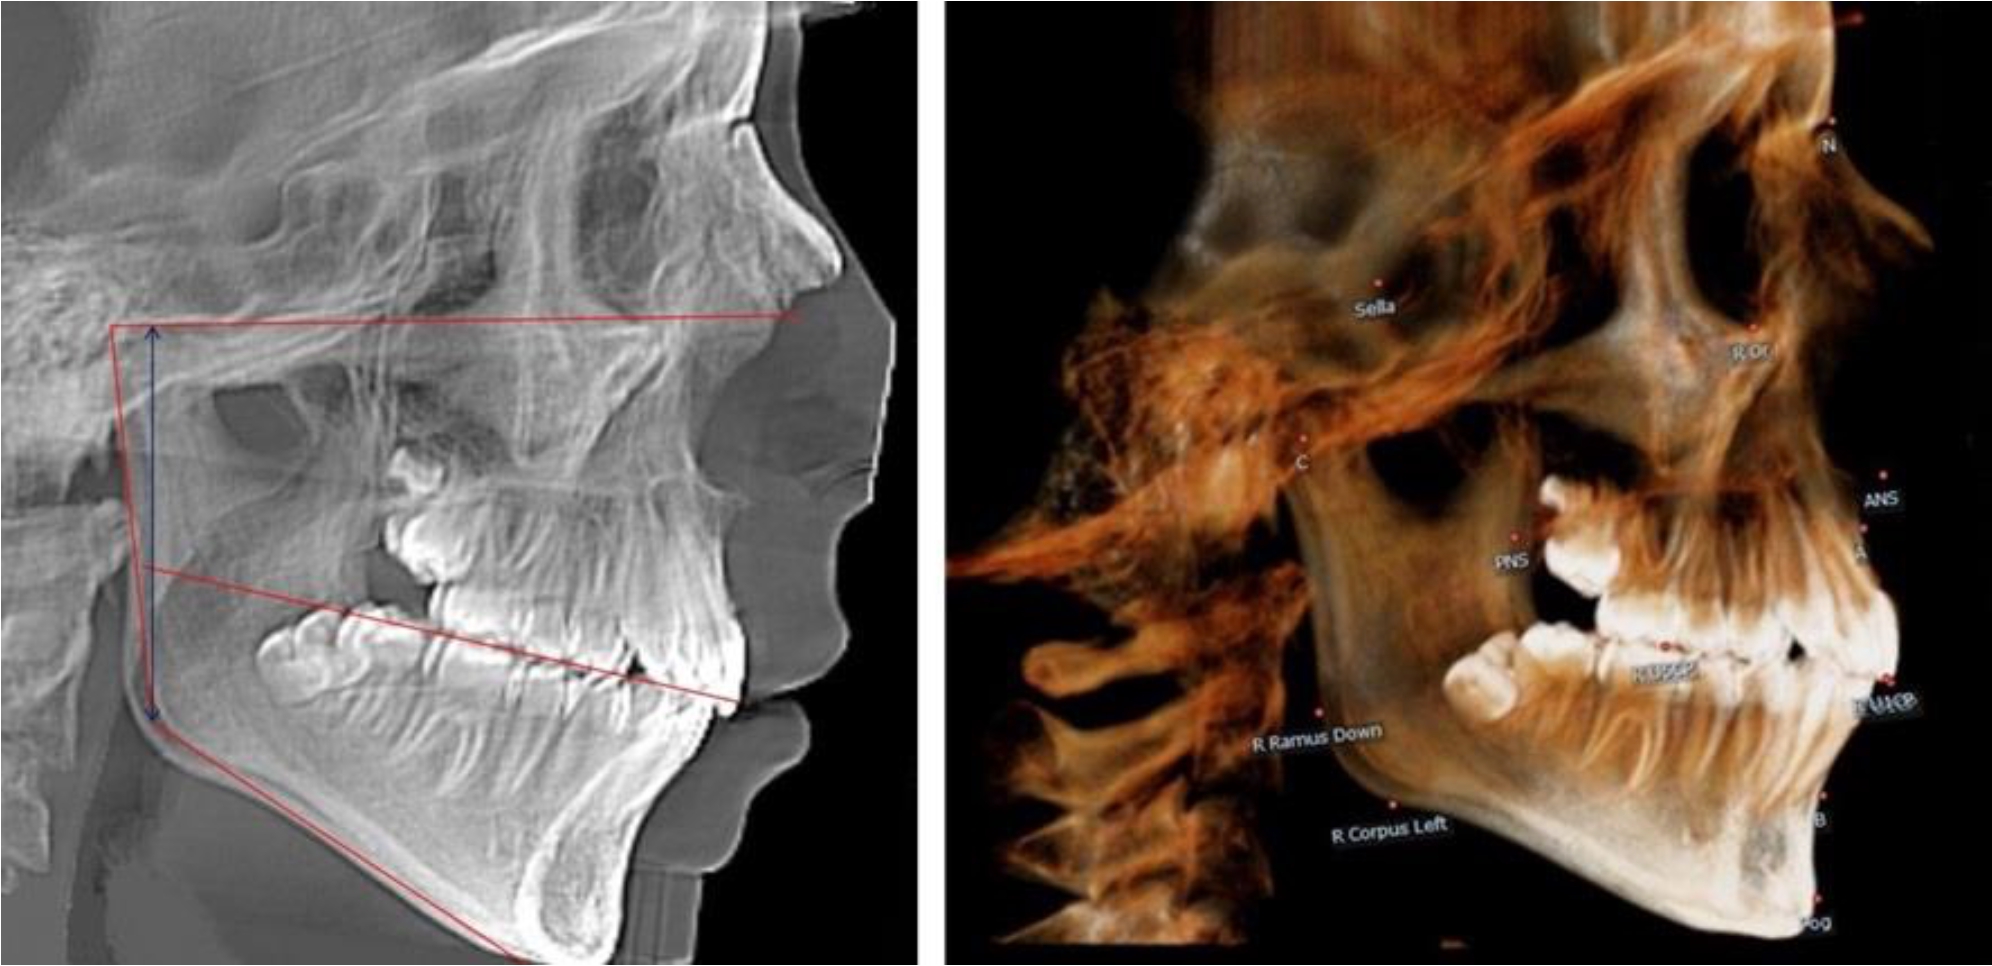

В 5-й группе были проанализированы 14 комплектов рентгенограмм, что составило (13,21 ± 3,29) % от общего числа. На всех рентгенограммах отмечен очередной этап подъема высоты прикуса, обусловленный прорезыванием вторых постоянных моляров. Окклюзионная линия делила ветвь на два отдела (рис. 5).

Рис. 5. ТРГ и ОПТГ пациента после смены молочных зубов и прорезывания вторых постоянных моляров

Высота ветви у детей 5-й группы составляла (62,87 ± 3,62) мм, что было достоверно больше, чем у детей других групп (р ˂ 0,05). При этом высота верхней окклюзионно-суставной части была (40,23 ± 2,01) мм, а нижней – (22,64 ± 1,78) мм. Высота верхней части была вдвое больше нижней, что и определяло особенности соразмерности частей ветви нижней челюсти в анализируемый возрастной период.

Относительные показатели соразмерности частей ветви нижней челюсти показали, что отношение высоты верхней части ветви к нижней в среднем составляло 1,78 ± 0,18. Отношение общей высоты ветви к верхней ее части составляло 1,56 ± 0,12, а отношение общей высоты ветви к нижней ее части было 2,78 ± 0,14, что и определяло особенности соразмерности частей ветви нижней челюсти в анализируемый возрастной период.

Таким образом, прорезывание постоянных зубов и смена молочных зубов постоянными изменяло не только высоту ветви нижней челюсти, но и изменяло соотношение ее частей, разделенных условной линией, являющейся продолжением окклюзионной линии рентгенограммы. Наиболее вариабельной структурой ветви являлась верхняя ее часть с суставным отростком. Окклюзионно-альвеолярная часть коррелировала с высотой зубочелюстных сегментов нижней челюсти.